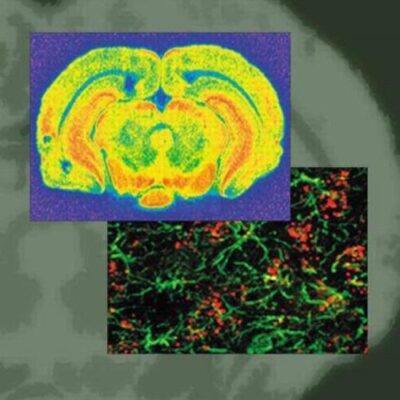

Explore the critical role of Borna Disease Virus (BDV) in neurobehavioral diseases with this essential scientific summary. ‘Borna Disease Virus: Role in Neurobehavioral Diseases’ from The Bookish Owl meticulously analyzes current research on BDV’s impact on the nervous system. Discover how this virus can lead to severe conditions, including fatal encephalitis and subtle yet significant behavioral disorders, often with minimal observable physical symptoms. This authoritative publication is a must-read for researchers, medical professionals, and anyone seeking in-depth knowledge on viral impacts on brain health. Understand the complex link between BDV and neurological conditions.